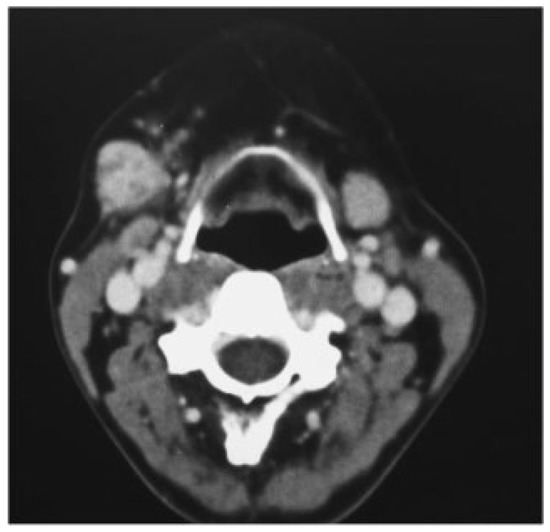

The mass was asymptomatic, and their size did not change during meals. On clinical examination,a firm well-defined mass was palpated measuring 2 cm diameter and with no fixation to the adjacent anatomic structures. FNA examination revealed for third time that the mass was pleomorphic adenoma of left parotid gland. CT scan detected a unique left parotid lesion, well defined of 1.2 × 1.8 cm of glandular tissue (Figure 2).

Figure 2. Left parotid tumor of 12 × 18 mm. Postsurgical changes in right parotid gland.